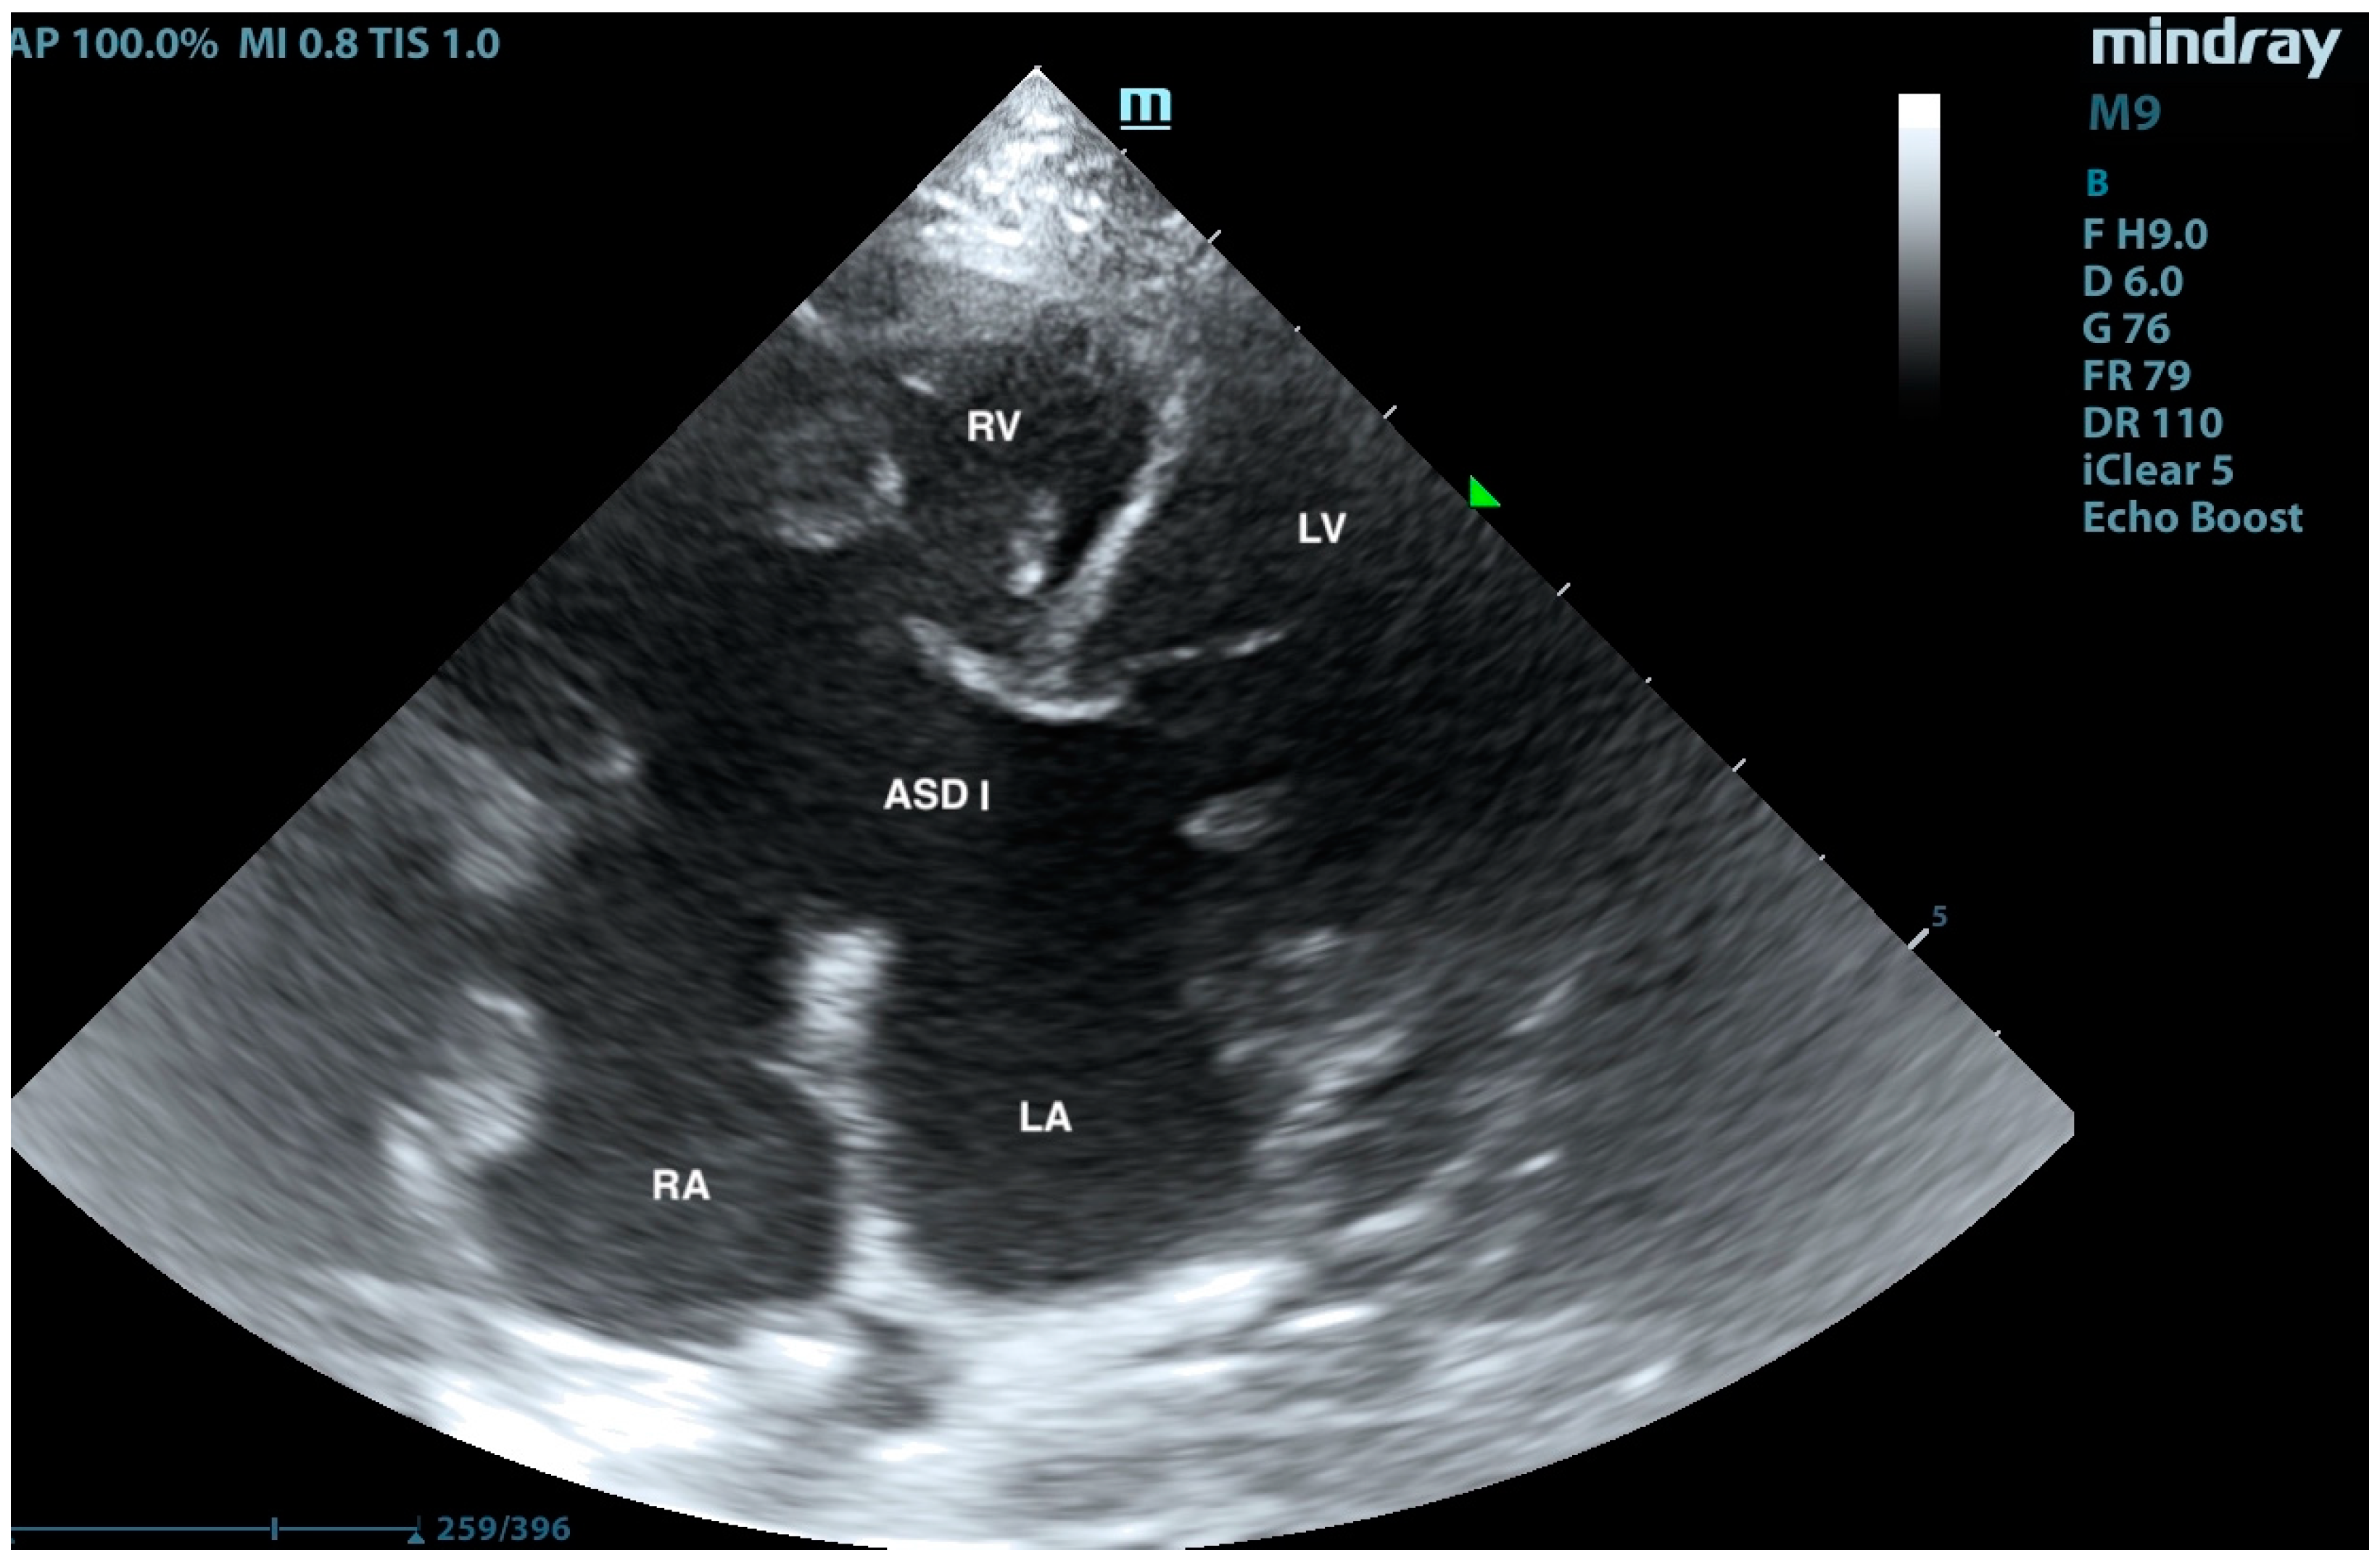

Pulmonary Artery Banding in a Cat with Atrioventricular Canal Defect Type A with Concurrent Muscular Septal Defect

2. Case Presentation